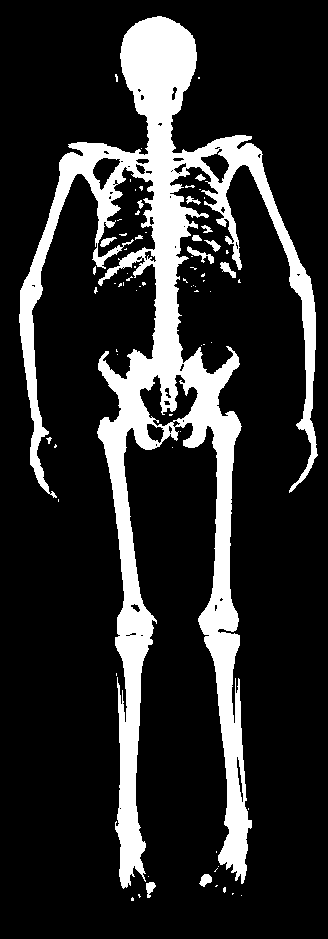

The key problem, however, is obtaining training data that simultaneously gives the inside and outside of the body in 3D. Most imaging technologies that simultaneously capture the inside and outside of the body use ionizing radiation, which is harmful to humans; e.g. Computed Tomography (CT) and X-rays. This means that such data is extremely limited, preventing learning-based methods. Our insight is to use dual-energy X-ray absorptiometry (DXA) data. DXA scans use low-dose X-rays to measure bone mineral density and body fat composition. The radiation level is so low that it is certified to be used on healthy patients for clinical studies, such as the UK Biobank [36]. In a DXA scan, two images are computed by combining two different energy levels: a soft-tissue image and a bone image (Fig. 2). In the silhouette of the body can clearly be seen, whereas reveals the structure and shape of the bones.

From the input images (, ), we compute the corresponding skin and skeleton segmentation masks (, ). For the skin mask , we threshold . As some small artifacts remain, mainly due to pixels in the lungs with low intensity values, we detect the closed contours on the image and fill in small areas. In Fig. 2 we show pairs of input and the obtained mask .